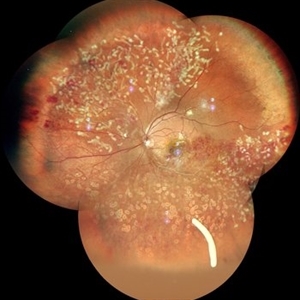

RPE rip in a case of Idiopathic polypoidal choroidopathy RPE rip in a case of Idiopathic polypoidal choroidopathyOct 23 2022 by Anjana Mirajkar, MS Ophthalmology Color photo central image in a of 61 year old male with RPE rip in a case of Idiopathic Polypoidal Choroidopathy. Photographer: Dr. Anjana Mirajkar -Retina Foundation, Ahmedabad Condition/keywords: idiopathic polypoidal choroidopathy, RPE Rip